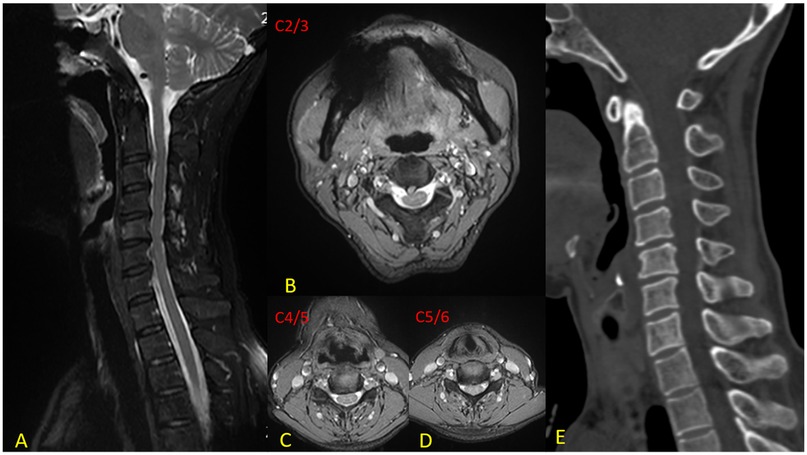

Background Cervical disc herniation at the C2-3 level, resulting in cervical spondylotic myelopathy (CSM), is an uncommon clinical entity. The diagnostic and therapeutic complexity escalates when this pathology coexists with non-contiguous multilevel cervical disc degenerative disease (CDDD). Due to the segmental variability in pathological features, the clinical manifestations of such cases are highly heterogeneous, thereby necessitating a highly individualized treatment strategy. Hybrid surgery (HS), which integrates cervical disc arthroplasty (CDA) and anterior cervical discectomy and fusion (ACDF), offers a tailored approach for the management of multilevel degenerative cervical pathology. The unique anatomical features and surgical technical challenges at the C2-3 level impose significant constraints on treatment options. This article presents a case of non-contiguous three-level hybrid surgery involving CDA at C2-3 and ACDF at C4-5 and C5-6, and discusses the feasibility of this technique for upper cervical disc pathology. Case Presentation A 62-year-old female was admitted with a 6-month history of neck and right upper limb pain, numbness, and gait instability, which had been unresponsive to conservative management. DR revealed loss of the normal cervical lordosis. CT showed no significant osteophyte formation or bony canal stenosis. MRI demonstrated a large disc extrusion at C2-3 causing spinal cord compression, and disc herniations at C4-5 and C5-6 with nerve root impingement. Based on clinical and imaging findings, a diagnosis of multilevel cervical spondylopathy (C2-3, C4-5, and C5-6 disc herniation) was established. The patient underwent anterior cervical discectomy followed by artificial disc arthroplasty (CDA) at C2-3, and anterior cervical discectomy and fusion (ACDF) at C4-5 and C5-6, successfully completing a non-contiguous three-level hybrid surgical procedure. Results Postoperative symptoms were significantly alleviated. At the 12-month follow-up, pain and gait disturbance had largely returned to normal. MRI confirmed adequate decompression of neural compression, DR demonstrated satisfactory range of motion (ROM) at C2-3, and CT revealed satisfactory bone healing at the fused segments. Conclusion CDA serves as an effective alternative for C2-3 disc pathology, achieving neural decompression while preserving segmental mobility. The HS provides a valuable surgical option for the precise treatment of non-contiguous multilevel degenerative disease.